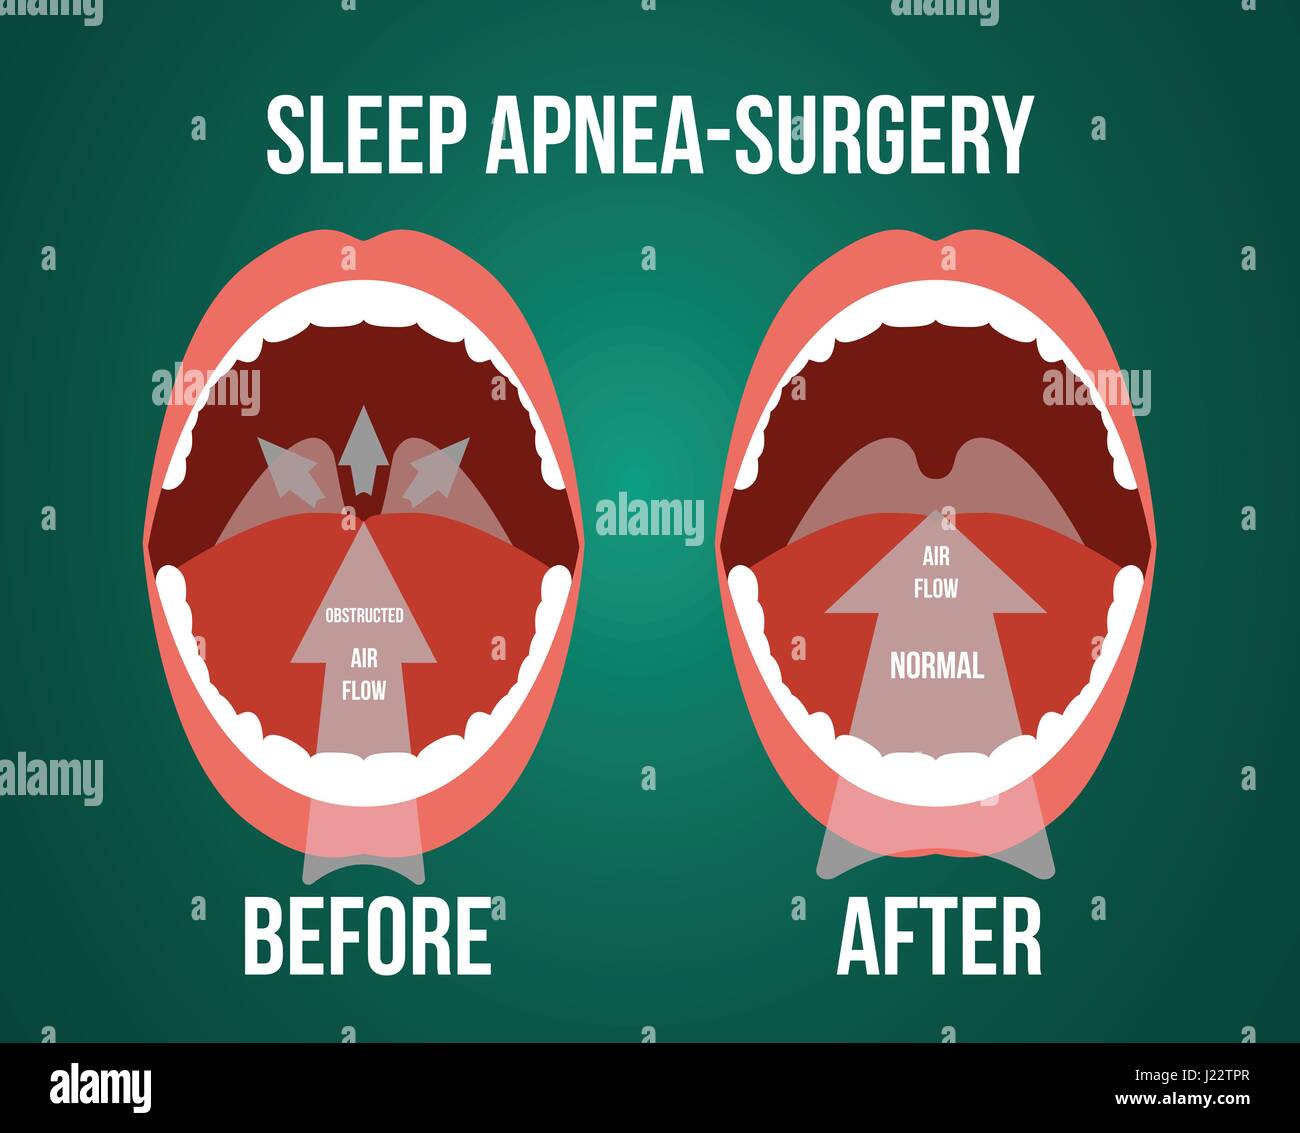

Vector illustration of surgery for obstructive sleep apnea, before and after result. Stock Vectorhttps://www.alamy.com/image-license-details/?v=1https://www.alamy.com/stock-photo-vector-illustration-of-surgery-for-obstructive-sleep-apnea-before-138975615.html

Vector illustration of surgery for obstructive sleep apnea, before and after result. Stock Vectorhttps://www.alamy.com/image-license-details/?v=1https://www.alamy.com/stock-photo-vector-illustration-of-surgery-for-obstructive-sleep-apnea-before-138975615.htmlRFJ22TPR–Vector illustration of surgery for obstructive sleep apnea, before and after result.